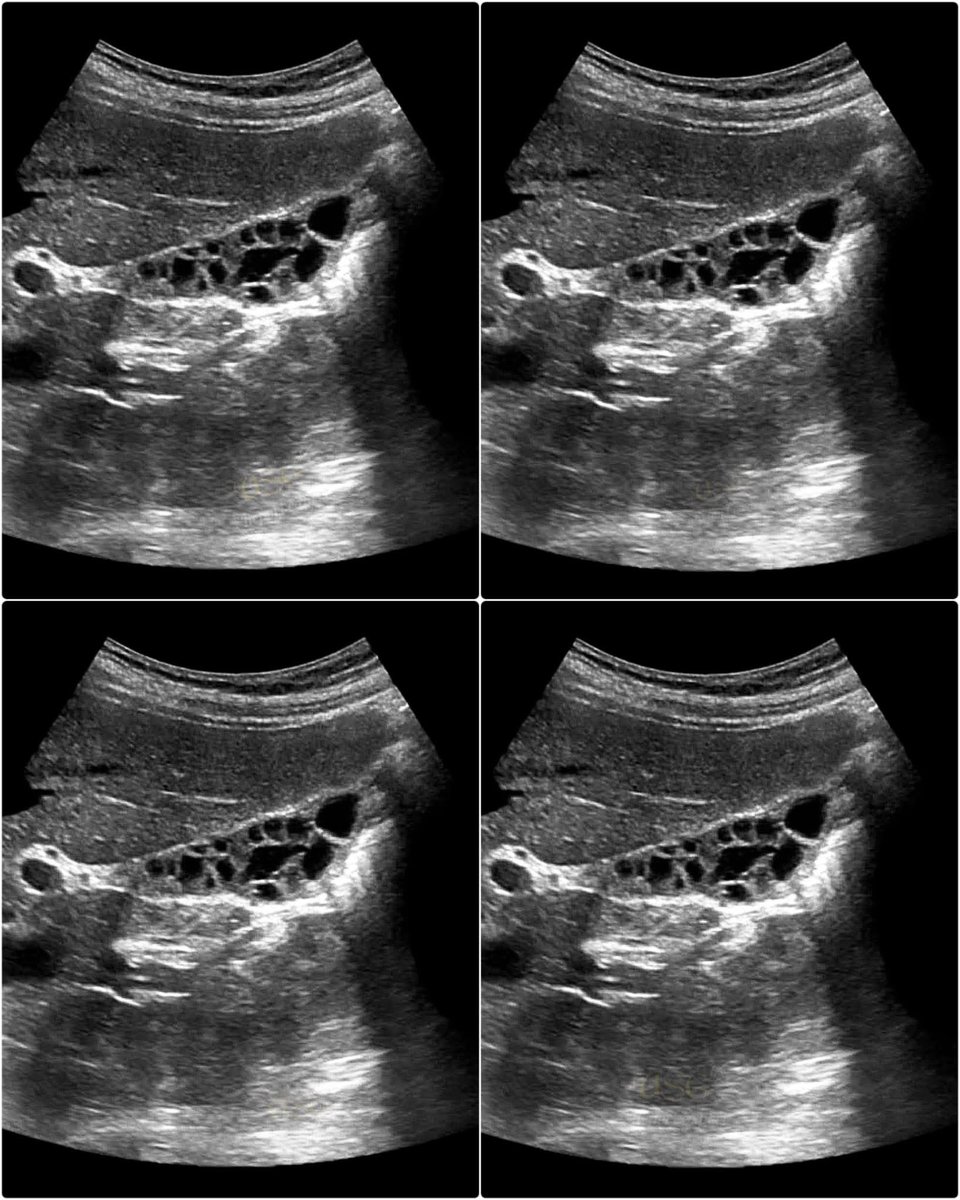

honeycomb gallbladder appears as a multiseptated gallbladder with a thickened wall and multiple non-shadowing echogenic septa (internal walls) crisscrossing the lumen. #EchoTech

honeycomb gallbladder appears as a multiseptated gallbladder with a thickened wall and multiple non-shadowing echogenic septa (internal walls) crisscrossing the lumen. #EchoTech

honeycomb gallbladder appears as a multiseptated gallbladder with a thickened wall and multiple non-shadowing echogenic septa (internal walls) crisscrossing the lumen. #EchoTech